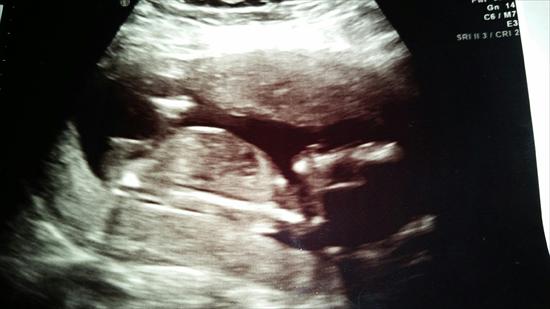

Confirmed Girl Nub! :)

After thinking SHE was a HE the first scans (12w and 13w) IT's A GIRL! This picture was taken at 14w3d (which I though, this is a girl!) and the MaterniT21 test was taken the same day and the result came back in 7 calendar days yesterday and confirmed she is a girl and the results were negitive! We already have a DS (4.5yo) named Drake Logan, and he really wanted a baby sister, so he is so happy! One of each!

Freya Evangeline! :ttcgirl::ttcgirl: :DD:

Attachment 20318